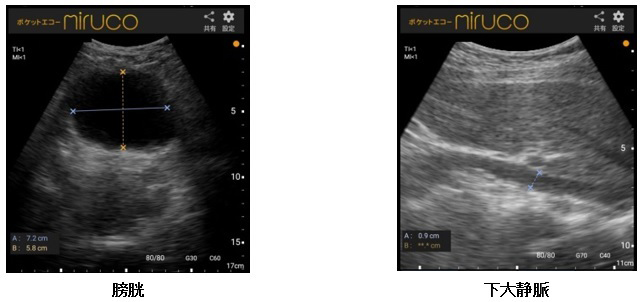

タブレット画面の描出画像の始点と終点の2点を指で合わせるだけで,2方向まで簡単に描出対象を計測できる。計測後に保存ボタンをタップすれば,計測結果はエコー画像と共にJPEGファイルで保存されるため,日常的に計測される場合には便利な機能である(面積・体積等の計算機能はない)。